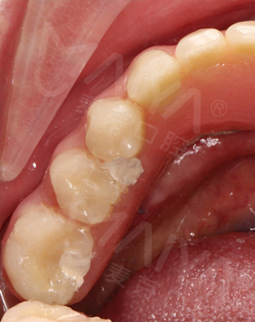

但是打完麻药,躺在那里发现手术时一点感觉也没有,半口牙只种了5颗牙钉,而且不到一个小时,感觉自己就眯了一会就好了。麦芽的种植专家们手法特别棒,很稳。牙钉种好之后,没有立即戴牙冠,医生用硅橡胶取模,为我制作了临时牙冠,不过看到临时牙冠我就能想象到完全种好牙的样子了!然后,医生给我一个小卡片,上面记录了种牙后的注意事项,告诉我种完牙后自己维护也很重要。医生说要按时复诊,也会有专门的工作人员进行通知,不得不说麦芽在细节上真的很暖心。

我种牙后并没有什么不适,下牙的牙齿种好了,我又找麦芽的硕博专家把上牙的几颗牙齿也种了,绝对不能因为一颗坏牙再引发其他的口腔问题。临时牙冠佩戴没有任何不适,做了永久修复,而且麦芽的硕博专家还给我分析下牙和上牙的咬合关系,不能随便就戴牙冠,种的好是一方面,更重要的是咬合和使用功能。